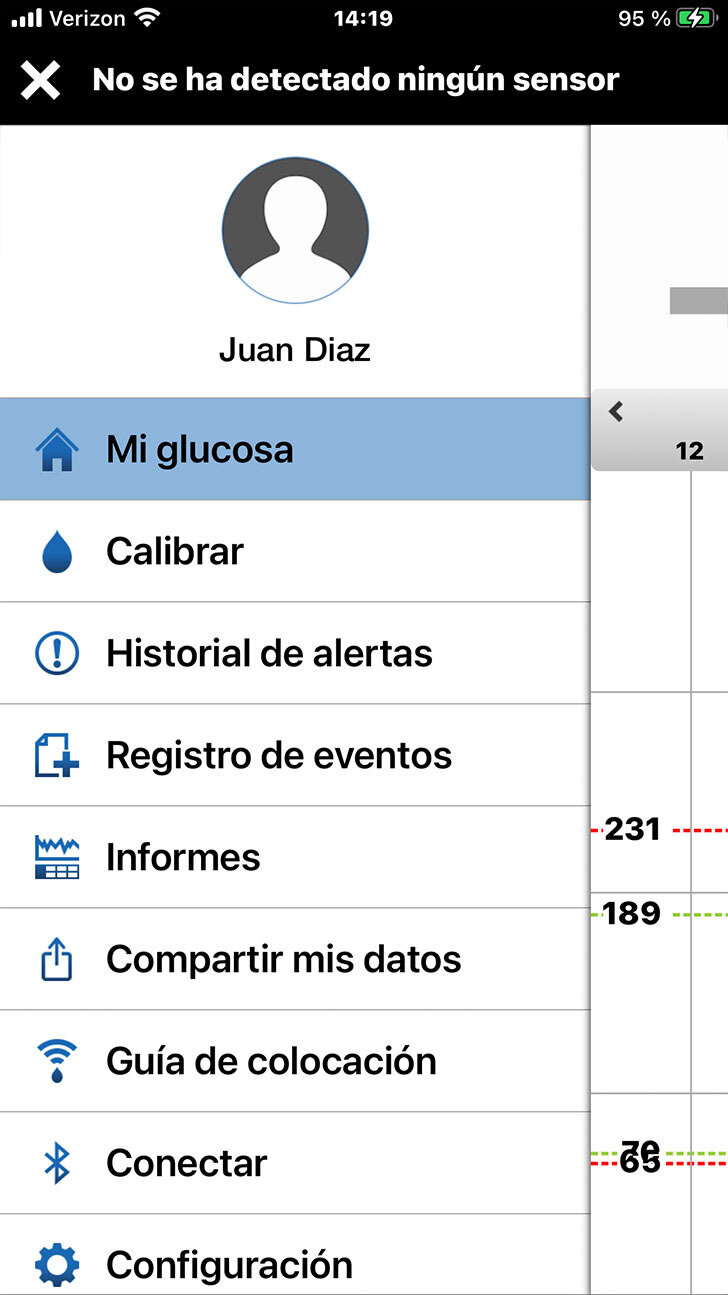

Para ir a su configuración personalizada, toque el icono de menú para abrir el Menú Principal.

Desplácese hacia abajo y toque Configuración.

Para ir a su configuración personalizada, toque el icono de menú para abrir el Menú Principal.

Desplácese hacia abajo y toque Configuración.

Para ir a su configuración personalizada, toque el icono de menú para abrir el Menú Principal.